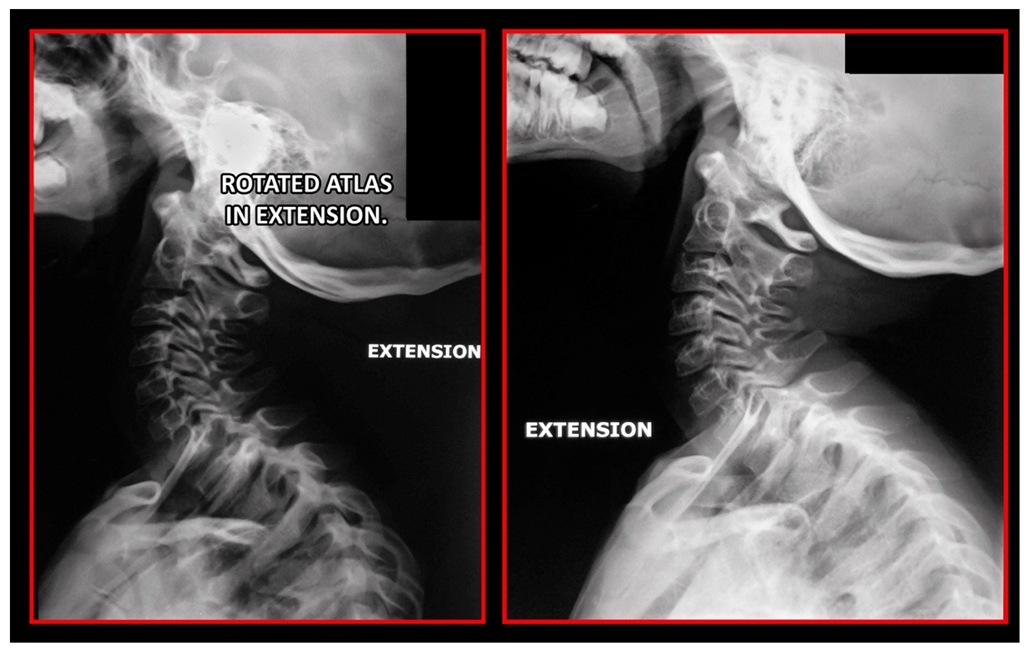

11.5. Axis and Atlas Derotation